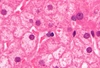

hemoglobin imbibition

血紅素浸透:

- pinkish to reddish coloration imparted to tissues due to the lysis of red blood cells.

- beginning some hours after death

- 不會用肉眼確認是否病變或死後變化,會在切片下確認

- especially the heart and arteries (particularly evident in the aorta) and veins